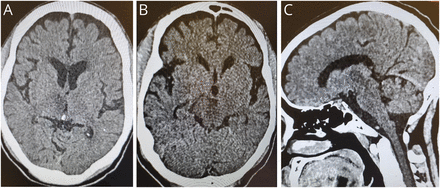

头部CT扫描显示右丘脑局灶性低密度,提示梗死,包括其靠近第三脑室壁的内侧部分,如轴向切片所示(图2一个),并延伸至中脑的嘴侧部,见四叉神经池水平的轴向切面(图2 b)和矢状面(图2 c).